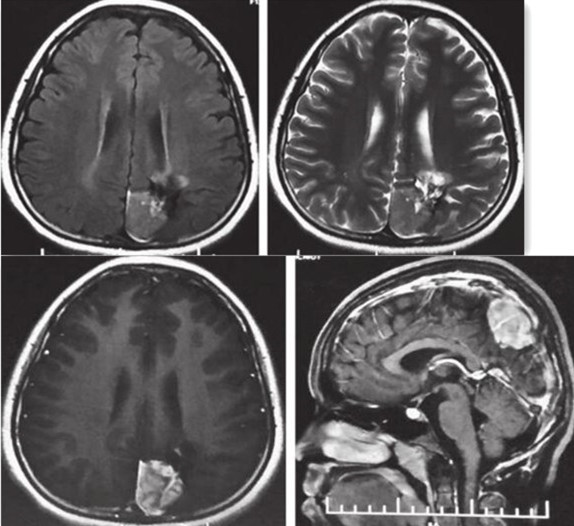

图2 2015-3-18 MRI检查图像,提示左顶叶占位合并陈旧性出血及囊变

图3 MRI示左顶叶异常信号团块表现同2015-3-18相仿,团块向左前方突入左侧脑室后角

图4 MRV提示上矢状窦近窦汇上方显示不连续,提示受压改变